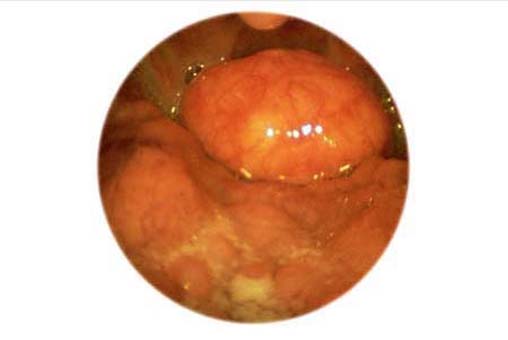

Zungengrundstruma . ........ Zum Kapitel